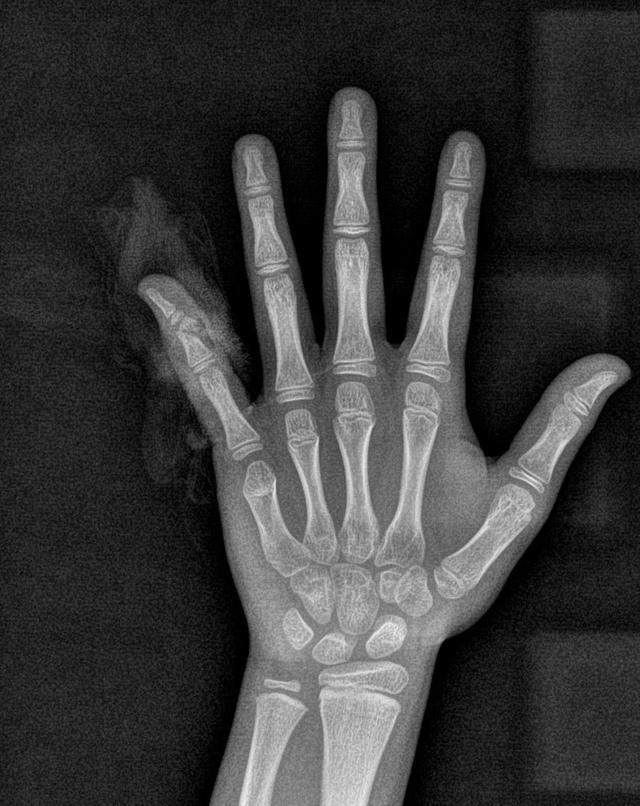

x线检查结果显示手指离断伤